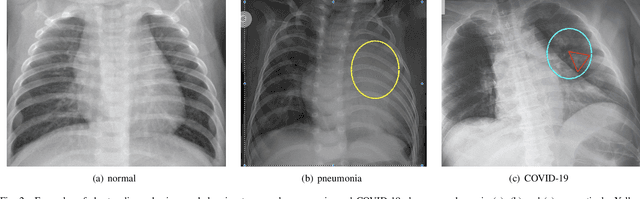

Abstract:Coronavirus disease 2019 (COVID-19) is an ongoing global pandemic in over 200 countries and territories, which has resulted in a great public health concern across the international community. Analysis of X-ray imaging data can play a critical role in timely and accurate screening and fighting against COVID-19. Supervised deep learning has been successfully applied to recognize COVID-19 pathology from X-ray imaging datasets. However, it requires a substantial amount of annotated X-ray images to train models, which is often not applicable to data analysis for emerging events such as COVID-19 outbreak, especially in the early stage of the outbreak. To address this challenge, this paper proposes a two-path semi-supervised deep learning model, ssResNet, based on Residual Neural Network (ResNet) for COVID-19 image classification, where two paths refer to a supervised path and an unsupervised path, respectively. Moreover, we design a weighted supervised loss that assigns higher weight for the minority classes in the training process to resolve the data imbalance. Experimental results on a large-scale of X-ray image dataset COVIDx demonstrate that the proposed model can achieve promising performance even when trained on very few labeled training images.